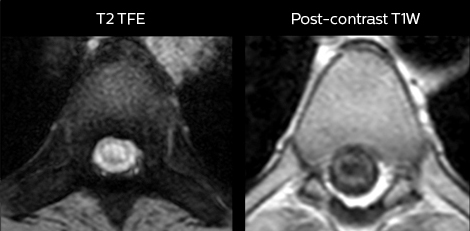

“We use mDIXON TSE extensively in our spine imaging in the emergency room,” says Dr. Karis. “It’s particularly nice in that it is very robust with regard to susceptibility type of problems that would come up with traditional spectral fat-saturated images; these problems are essentially eliminated with the mDIXON technique. In our ED environment it’s really nice to have the fat-free imaging that goes along with the mDIXON technique.

“For the thoracic and cervical spine routine non-contrast exam, for example, we perform one mDIXON T2 TSE sequence, which provides us with two outputs: the fat-and-water-together T2-weighted images, as well as the water-only sagittal T2-weighted images. And then we also perform an axial gradient echo exam.”